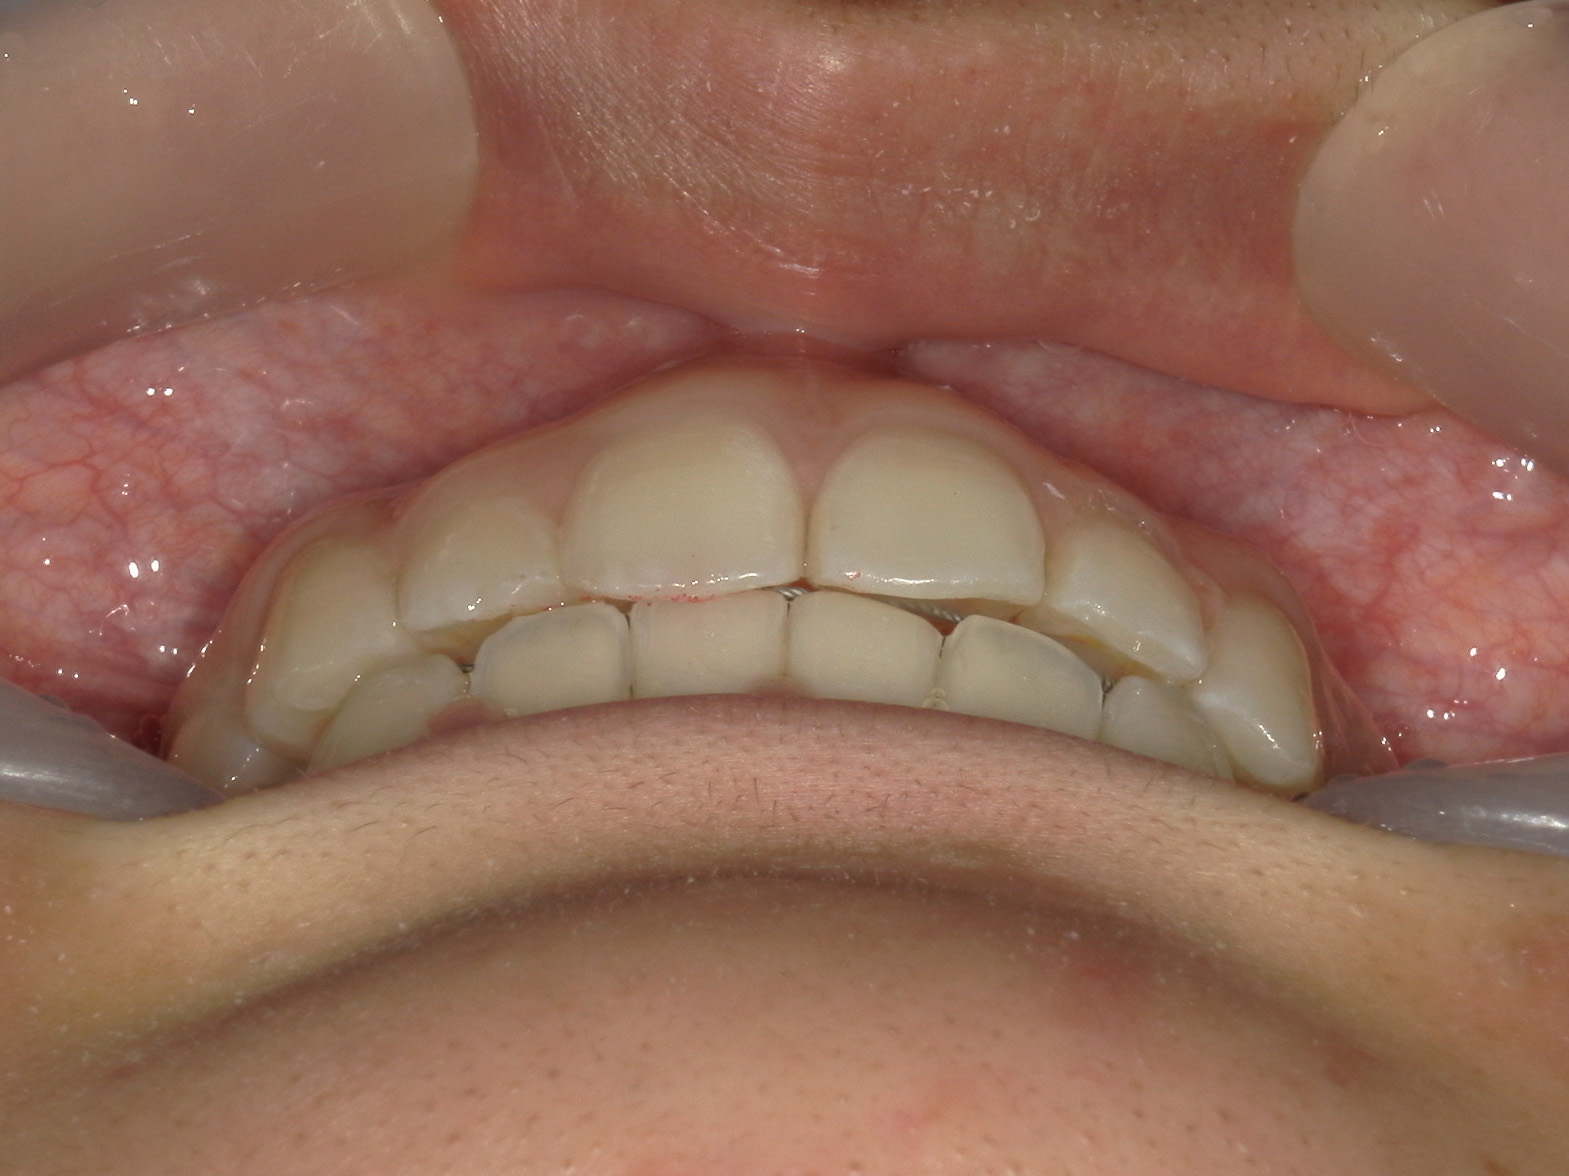

プチワイヤー矯正 症例(54)

主訴: 歯並びが気になる。

ミニインプラント(2本)、スライスカットを併用。

カテゴリー : ガタガタ(叢生)